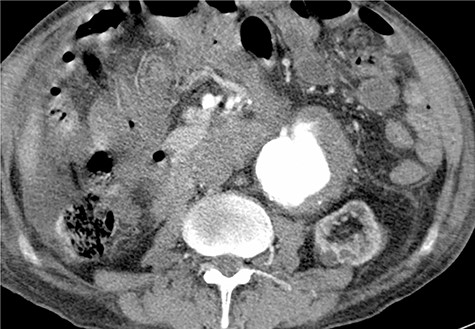

A 59-year-old male presented with end-stage liver disease secondary to hepatitis C and end-stage renal disease. On CT scan, an abdominal aortic aneurysm was incidentally found with a diameter of 4*3.8 cm (Fig. 1).